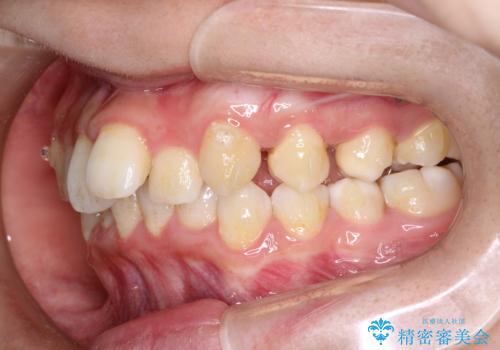

重度のガタガタのインビザラインによる非抜歯矯正

- 全体的なガタガタを気にされて来院されました。

抜歯矯正も考えられる状態でしたが、ご本人的になるべく歯を抜かない矯正を希望されました。

奥歯を後方に移動させるのと、歯と歯の間にわずかに隙間を作ることでスペースを確保して、抜歯をせず歯を並べる計画としました。

ガタガタの度合いが大きかったので少し時間がかかりましたが、非常に協力的な患者様でしたので、抜歯をせず計画通りに治療を終えることができました。